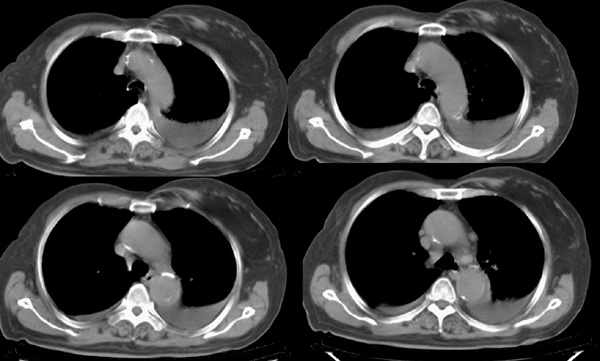

以下是引用panyishengct在2008-5-19 21:48:00的发言:[br]左侧胸壁脂肪瘤;肺部还是考虑肺水肿,胸腔积液。 [br] [br]左肺门见一团状影,纵隔见淋巴结,建议治疗后复查,以排外中央型肺癌

以下是引用形影不离在2008-5-19 21:13:00的发言:[br]左侧胸壁脂肪瘤;肺部还是考虑心衰并肺水肿,胸腔积液。